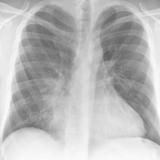

Case 2 PA